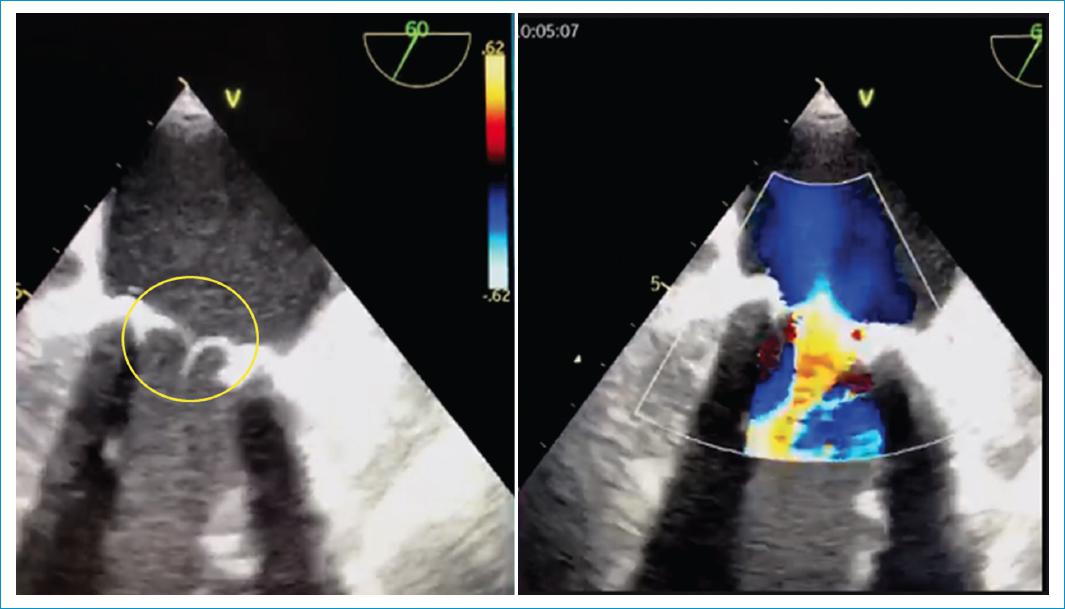

Paciente de sexo masculino, de 49 años, sin antecedentes patológicos, quien consultó por cuadro clínico de quince días de evolución, caracterizado por picos febriles recurrentes, con deterioro de su clase funcional, asociado a dolor torácico, pérdida de la fuerza en miembros inferiores y posterior alteración del estado de consciencia. Al examen físico cardiovascular, se evidenció soplo holosistólico mitral, por lo cual se ordenó un ecocardiograma transtorácico en el que se halló vegetación en la válvula mitral, con perforación del segmento A3 con jet de insuficiencia mitral grave y perforación del anillo mitral anterior con relación al segmento A3, ocasionando una fístula ventrículo-pericárdica con evidencia de derrame pericárdico circunferencial grave y presencia de flujo por Doppler color (Fig. 1; flecha amarilla), en la cavidad pericárdica con signos de taponamiento cardíaco (Fig. 2; flecha roja); ventrículo izquierdo hiperdinámico con fracción de eyección del 68%. Se realizó procedimiento quirúrgico para la resección de la vegetación y la confirmación del trayecto fistuloso con cierre de este usando parche de pericardio autólogo más reemplazo de válvula mitral con prótesis biológica # 27. El paciente tuvo una evolución satisfactoria. El ecocardiograma de control previo al egreso mostró prótesis biológica en posición mitral, normofuncionante (Fig. 3; círculo amarillo), sin fuga periprotésica ni evidencia de fistula residual (Fig. 3), con ventrículo izquierdo de grosor y cavidad normal, hipocinésica global y disfunción sistólica leve (FEVI 40%).